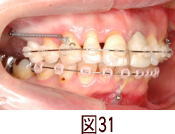

前歯の出っ張り具合が気になって来院された患者さんです。 |